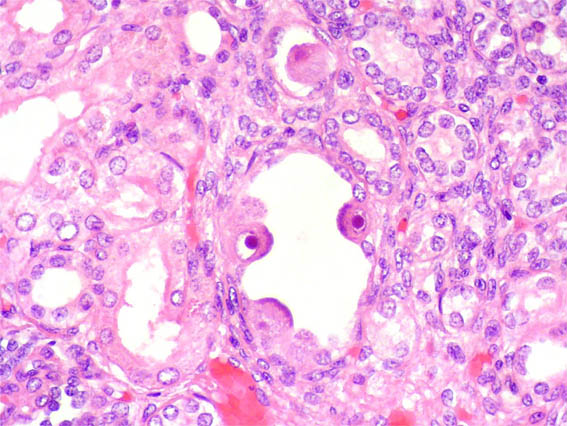

En ambos riñones fetales se observa lo mostrado en las siguientes imágenes.

Figura 2.

H&E, X400.